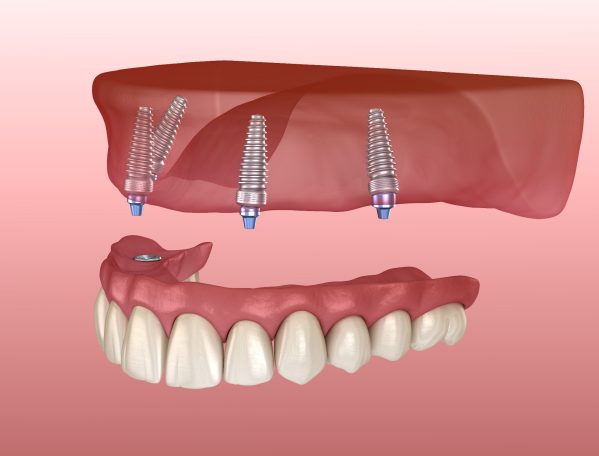

Brücken dienen dazu, fehlende Zähne zu ersetzen, indem sie an benachbarten Zähnen oder mehreren Implantaten befestigt werden und sorgen so für eine geschlossene und funktionale Zahnreihe. Kombinationszahnersatz ist vorteilhaft, da er sowohl aus festen als auch herausnehmbaren Komponenten besteht, um individuelle Bedürfnisse zu berücksichtigen, besonders wenn bereits eine größere Anzahl von Zähnen fehlt.

Prothesen hingegen sind ideal für Patienten, die mehrere bis alle Zähne verloren haben und bieten meist eine schnelle und kostengünstige Lösung zur Wiederherstellung der Kaufunktion und Ästhetik.

Zahnersatz auf eigenen Zähnen und Implantaten

Bei den implantatgestützten Versorgungen arbeiten wir vertrauensvoll mit unseren kompetenten Kollegen aus mehreren Greifswalder Oralchirurgie-Praxen zusammen.